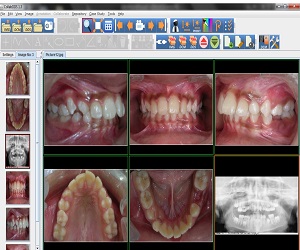

CollabDDS provides a real time collaborative environment to visualize medical (Skeletal) and dental images (digitized X-Ray images or DICOM data) for diagnosis and treatment planning. CollabDDS has various image processing tools to visualize the data and also annotate. An inbuilt repository of annotated images can be used for education. Further it enables real time collaboration for diagnosis between physician at PHC level and experts at medical colleges and hospitals. CollabDDS is unique as it allows the viewing and processing of digitized X-Rays in various standard image formats like JPEG and DICOM and also allows this data to be saved for later review/ study.

The first version of the CollabDDS V1.0 was released on July 04, 2012. Based on the continuous feedback from the experts, latest version 1.6 was released on August 19, 2014. Dental module for Cephalometric analysis has also been introduced in this version.

With the proof of concept having gone through successfully, a Pilot Project for Implementation of CollabDDS at Medical and Dental Colleges and Hospitals has been undertaken. This is an extension of the POC to the Operational Research Phase as a prelim to rollout. This pilot implementation is used to evaluate the efficiency and effectiveness of remote diagnosis. Further this phase also incorporates a module which carries out Cephalometric analysis for orthodontic surgeons to enable diagnosis and treatment planning of their patients. This phase would also include the Enhancement of CollabDDS and Advanced Applications on 3D imaging. It would involve the reconstruction of 3-D models from CT / Surface images, development of methodologies for orthopedic implant development using 3D models.